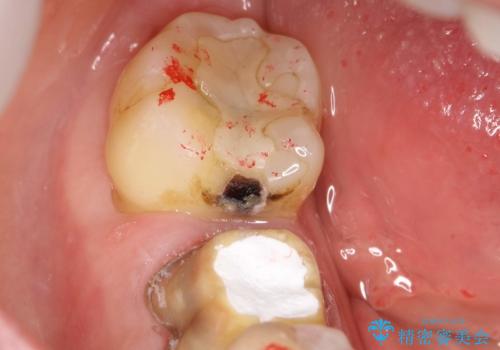

奥歯の詰め物が外れた PGAインレー修復

- クリーニングを希望し、来院された患者様です。

クリーニング中に他院で治療した古い詰め物が破折したため、やり替えをお勧めしました。

かみ合わせが強いことや上の奥歯であることからゴールドでのインレー修復を行いました。

ゴールドは保険のプラスチックの材料やセラミックと比較して破折のリスクがほとんどありません。

ただし、見た目に関してはセラミックに劣ります。